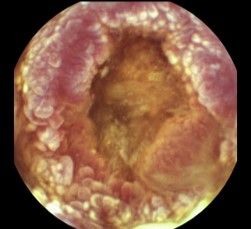

La principal indicación de la cápsula endoscópica de intestino delgado es la anemia, otras son la sospecha o control de enfermedad de Crohn, enfermedad celiaca refractaria, diarrea crónica, etc.

La principal indicación de la cápsula endoscópica de colon es la colonoscopia incompleta, otras son la negativa del paciente a realizar colonoscopia, pacientes con alto riesgo anestésico y que no puedan someterse a una exploración invasiva, etc.